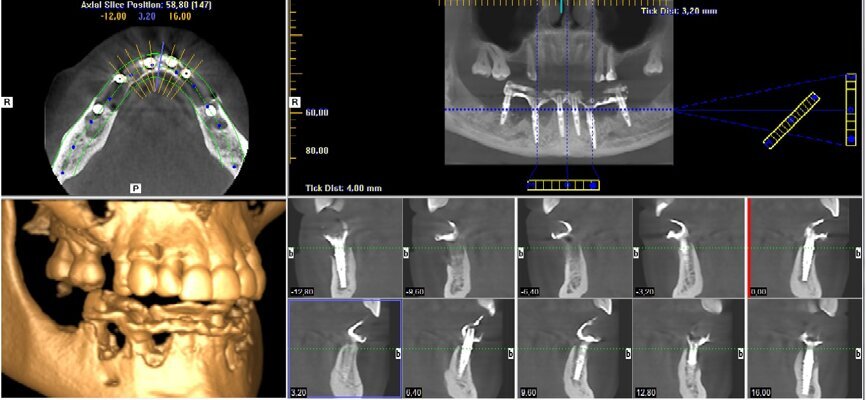

Wykonanie badania tomograficznego potwierdziło diagnozę o zaawansowanej nierokującej chorobie przyzębia (Ryc. 2). Po konsultacji została podjęta decyzja o ekstrakcji wszystkich zębów w żuchwie, natychmiastowym wprowadzeniu implantów z jednoczesną czasową odbudową protetyczna stałą mocowaną na wszczepionych implantach. Zlecono rutynowe badanie lekarskie i laboratoryjne.